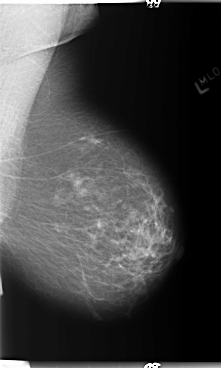

ics_version 1.0 filename B-3362-1 DATE_OF_STUDY 14 8 1997 PATIENT_AGE 77 FILM FILM_TYPE REGULAR DENSITY 2 DATE_DIGITIZED 4 6 1998 DIGITIZER LUMISYS LASER SEQUENCE LEFT_CC LINES 5936 PIXELS_PER_LINE 3304 BITS_PER_PIXEL 12 RESOLUTION 50 NON_OVERLAY LEFT_MLO LINES 5888 PIXELS_PER_LINE 3528 BITS_PER_PIXEL 12 RESOLUTION 50 NON_OVERLAY RIGHT_CC LINES 5896 PIXELS_PER_LINE 3040 BITS_PER_PIXEL 12 RESOLUTION 50 OVERLAY RIGHT_MLO LINES 5896 PIXELS_PER_LINE 3312 BITS_PER_PIXEL 12 RESOLUTION 50 OVERLAY |